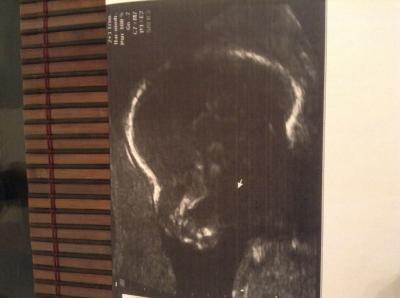

Hy Mädls, was für ein aufregender schöner Tag! Also meinen Zwerg geht es bestens, alles Zeitgerecht entwickelt... Organe schauen soweit auch gut aus näheres sehen wir dann beim Organscreening! Wir dachten ja alle das es ein Junge ist... Doch heute war es eindeutig eine kleine Prinzessin ich kann es gar nicht glauben hihi. Aber mir wAr es ganz egal was es wird ich hab mich zwa schon auf Jungen eingestellt gehabt aber die Freude ist jetzt genau so groß, hauptsache gesund :-) das ist das wichtigste! Meine Schwiegermama ist enttäuscht das es doch kein Junge ist... naja kann ich nicht nachvollziehen da wir einen langen Weg hatten überhaupt schwanger zu werden... Aber sie freut sich eh... Ich bin sooooo happyyyyyy werd jetzt gleich mal nach Mädchenklamotten schauen im Internet JUHUUUUUUUU Achja ich habe auch eine Vorderwandplazenta :-/ und mein Eisenwert war zu wenig muss jetzt tabletten nehmen... Sonst alles OK

Bild zu FA-Bericht mit Outing - Forum für April - Mamis